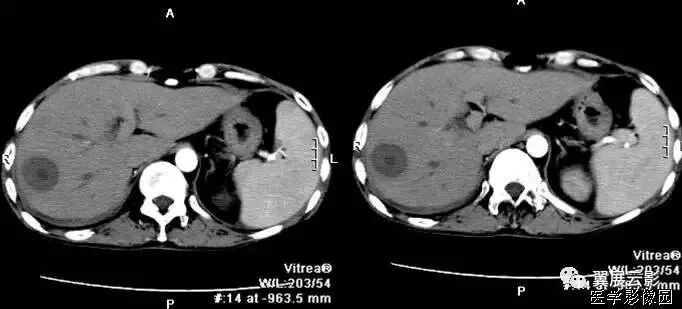

下图肠扭转病例:

下图是闭襻性的肠梗阻

闭袢型肠梗阻